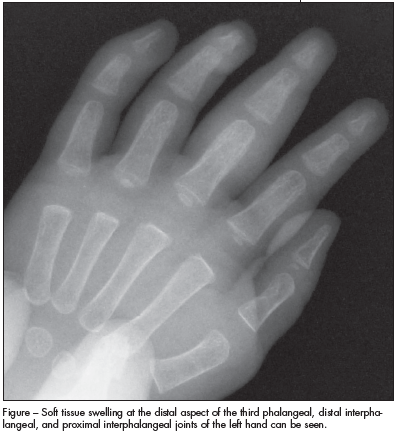

Radiograph of hands is shown.

ANSWER: JUVENILE IDIOPATHIC ARTHRITISThe radiograph showed soft tissue swelling at the distal aspect of the third phalangeal, distal interphalangeal, and proximal interphalangeal joints of the left hand (Figure). There were no bony abnormalities or joint-space widening. Radiographs of the left knee showed mild swelling and no fracture or dislocation. These findings suggested a diagnosis of juvenile idiopathic arthritis (JIA). The laboratory test results ruled out other possible causes of arthritis and arthralgia, including Lyme disease, systemic lupus erythematosus, and septic arthritis

On radiographic studies, the fingers are typically involved in monarticular or oligoarticular JIA, whereas the entire hand is affected in those with polyarticular JIA.6